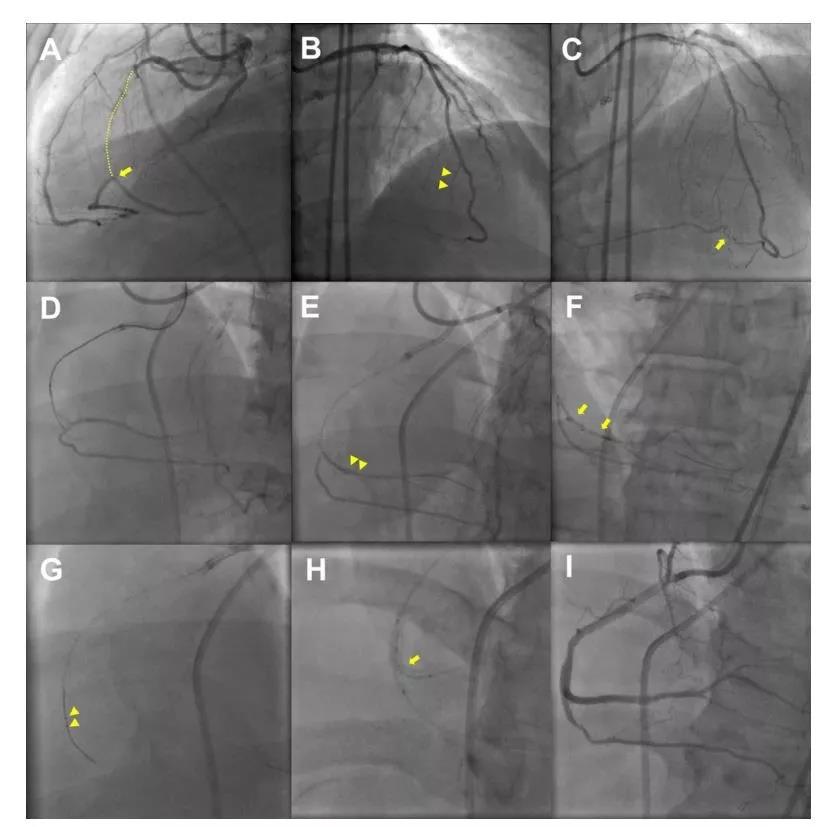

示意图介绍AFR步骤:A) 闭塞性血栓(黑色箭头);位于RCA中段; B) 第一根导丝(绿色)位于闭塞远端的内膜下(黑色箭头); C) 沿着第一根导丝送入球囊位于夹层的可能的重回真腔处 (黑色箭头); D) 聚合物护套的导丝 (白色箭头)在假腔推进,置于球囊前方 (黑色箭头); E) 球囊快速扩张和回抽造成真假腔之间的连通(白色箭头)。球囊回抽时,聚合物护套导丝(黑色箭头)推进入真腔; F) 实施常规PCI。AFR技术的使用是在医源性冠脉夹层传统方法无法重回真腔时的挽救性方法。